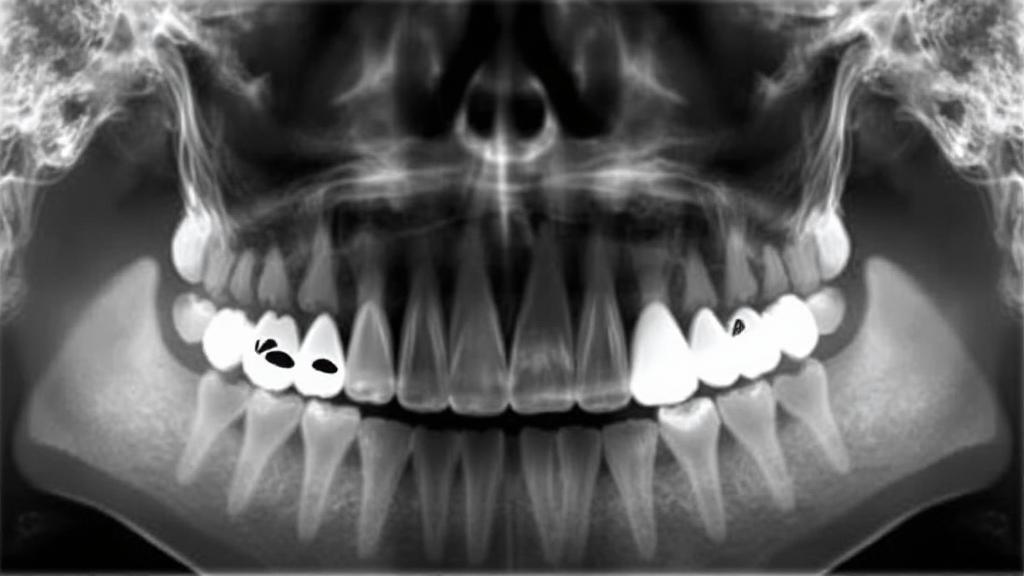

- Consultation: X-rays to assess position and determine treatment